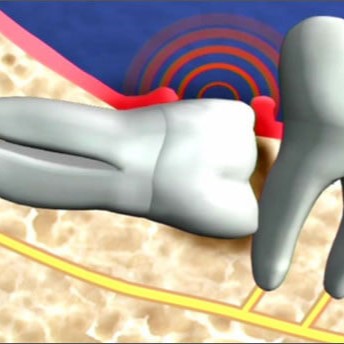

Răng khôn mọc ngang, mọc lệch: Sẽ đẩy vào răng số 7, gây ảnh hưởng cả hàm răng, có thể khiến chân răng số 7 bị ảnh hưởng, gây tiêu xương, viêm nhiễm hoặc nang chân răng

Răng khôn không thể mọc thoát ra ngoài, ngầm trong xương hàm: Sẽ hình thành nang quanh thân răng, nang quanh thân răng phát triển phá hủy toàn bộ xương góc hàm.